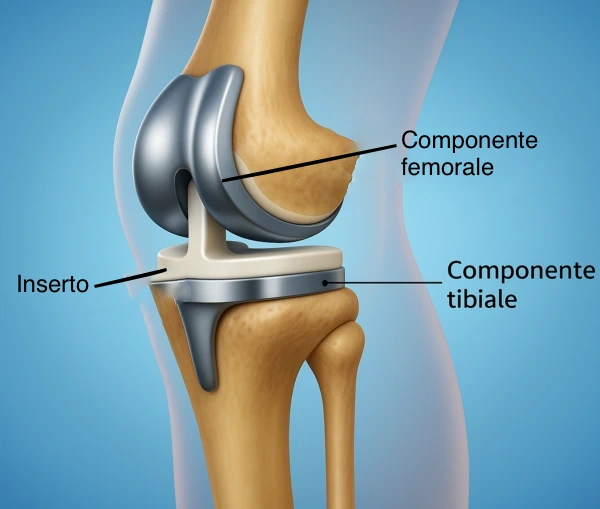

Se necessario, il difetto osseo creato può essere colmato con innesto di osso allograft (da donatore) o sintetico. Si ricorre all’osteotomia come intervento di salvataggio in alternativa o in attesa di un intervento di protesi di ginocchio, in un quadro di artrosi di ginocchio con presenza di ginocchio “varo” o “valgo”.

L’intervento è particolarmente indicato per chi vuole posticipare l’impianto di una protesi e mantenere un buon livello di attività fisica, anche sportiva.

Preservazione dell’articolazione naturale, ritardando o evitando la necessità di una protesi.

Chi presenta dolore da disallineamento e vuole evitare una protesi totale.

L’osteotomia del ginocchio rappresenta una valida alternativa alla protesi per pazienti giovani e attivi con deformità dell’asse dell’arto inferiore. Correggendo l’allineamento, ridistribuisce i carichi sull’articolazione e rallenta la degenerazione, permettendo un ritorno a una vita attiva e sportiva. È un intervento altamente personalizzato che richiede una valutazione ortopedica specialistica e una pianificazione chirurgica accurata.